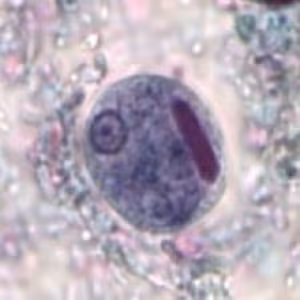

2019 DPDx Case Studies

DPDx is an educational resource designed for health professionals and laboratory scientists. For an overview including prevention, control, and treatment visit www.cdc.gov/parasites/.